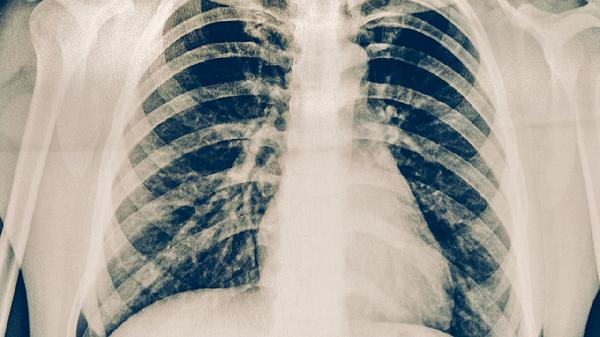

肋骨骨折患者应注意休息与适当活动的平衡。恢复期间可以适当散步促进血液循环,但需控制活动强度与时间。饮食上应增加富含钙质与优质蛋白的食物如牛奶、鱼肉等,有助于骨折愈合。定期复查X线片观察骨折愈合情况,如有持续胸痛或呼吸困难应及时就医。